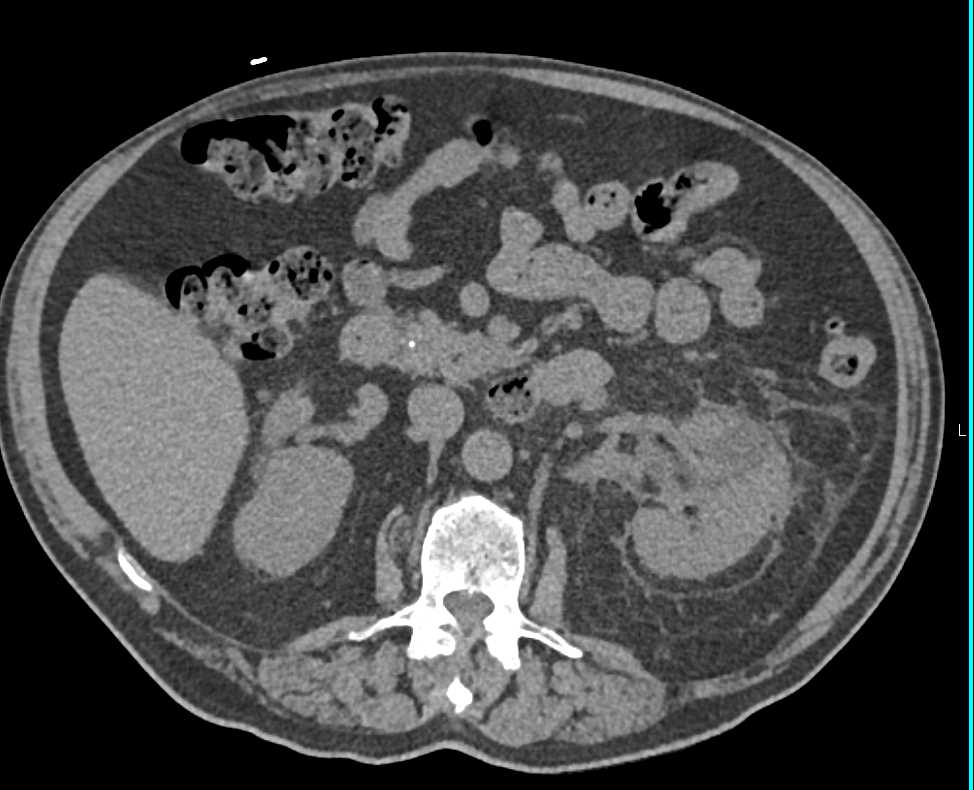

Left Renal Cell Carcinoma Invades the Left Renal Vein